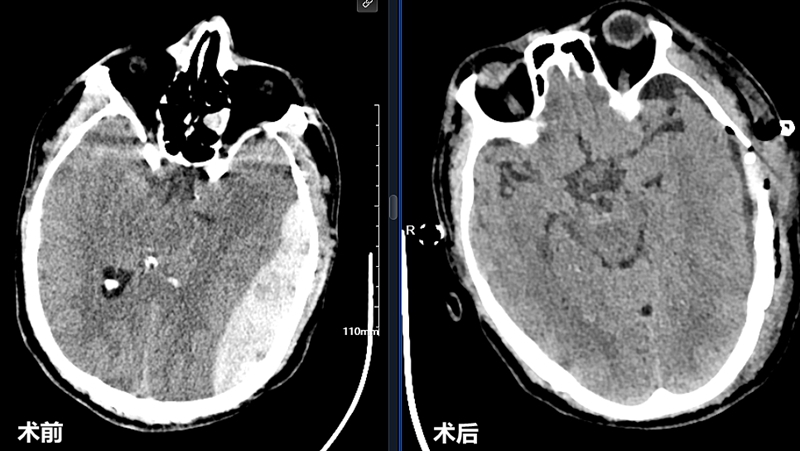

神经外科主治医师林邵奇收到通知火速赶到,结合CT结果快速确诊:脑外伤导致左侧硬膜外脑血肿!“当时血肿量不断增加,脑组织受挤压明显,左侧脑室已被压迫变形。”林邵奇解释,费大爷的情况必须马上手术,再晚就会引发脑疝,造成不可逆转的神经损伤,甚至能直接夺走生命。

神经外科副主任医师陈思强与主治医师林邵奇联手上台,连夜实施开颅减压术 + 脑血肿清除术。

两个多小时内,手术团队全神贯注、精准操作,成功清除颅内血肿,解除患者生命危险,术后其被立即转入ICU进行严密监护。